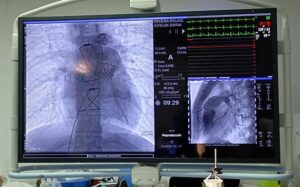

Especialistas de la Unidad Médica de Alta Especialidad (UMAE) Hospital de Especialidades No. 71 del Instituto Mexicano del Seguro Social (IMSS) en Torreón, Coahuila, realizaron por primera vez el reemplazo e implantación de válvula pulmonar mediante un procedimiento mínimamente invasivo, para corregir un defecto cardiaco congénito llamado Tetralogía de Fallot a dos jóvenes.

Este procedimiento sustituye a la operación a corazón abierto que implica mayores riesgos para el paciente y con ello esta Unidad Médica de Alta Especialidad (UMAE) se convirtió en el primer hospital del Instituto en el norte del país en efectuar esta cirugía de alta complejidad.

El jefe del Servicio de Hemodinamia de esta UMAE, doctor Alberto Bazzoni Ruiz, explicó que el pasado 6 de marzo, Evelin “N” de 18 y Luis “N” de 19 años, ambos de Durango, fueron los primeros pacientes en ser intervenidos con este procedimiento que se realiza mediante una punción en la vena femoral (ingle) como vía de acceso hasta el corazón, a fin de implantar la prótesis de la válvula que se va a reemplazar o reparar sin necesidad de abrir el tórax y exponer el corazón, como se hacía en el pasado.

En marzo de este año, el doctor Teodoro de Jesús Alvarenga, cardiólogo intervencionista con alta especialidad en cardiopatía congénita y un equipo multidisciplinario encabezado por el doctor Bazzoni Ruiz realizaron la colocación de válvula pulmonar transcateter a Evelin y Luis, procedimiento que se efectuó en menos de una hora en cada caso.